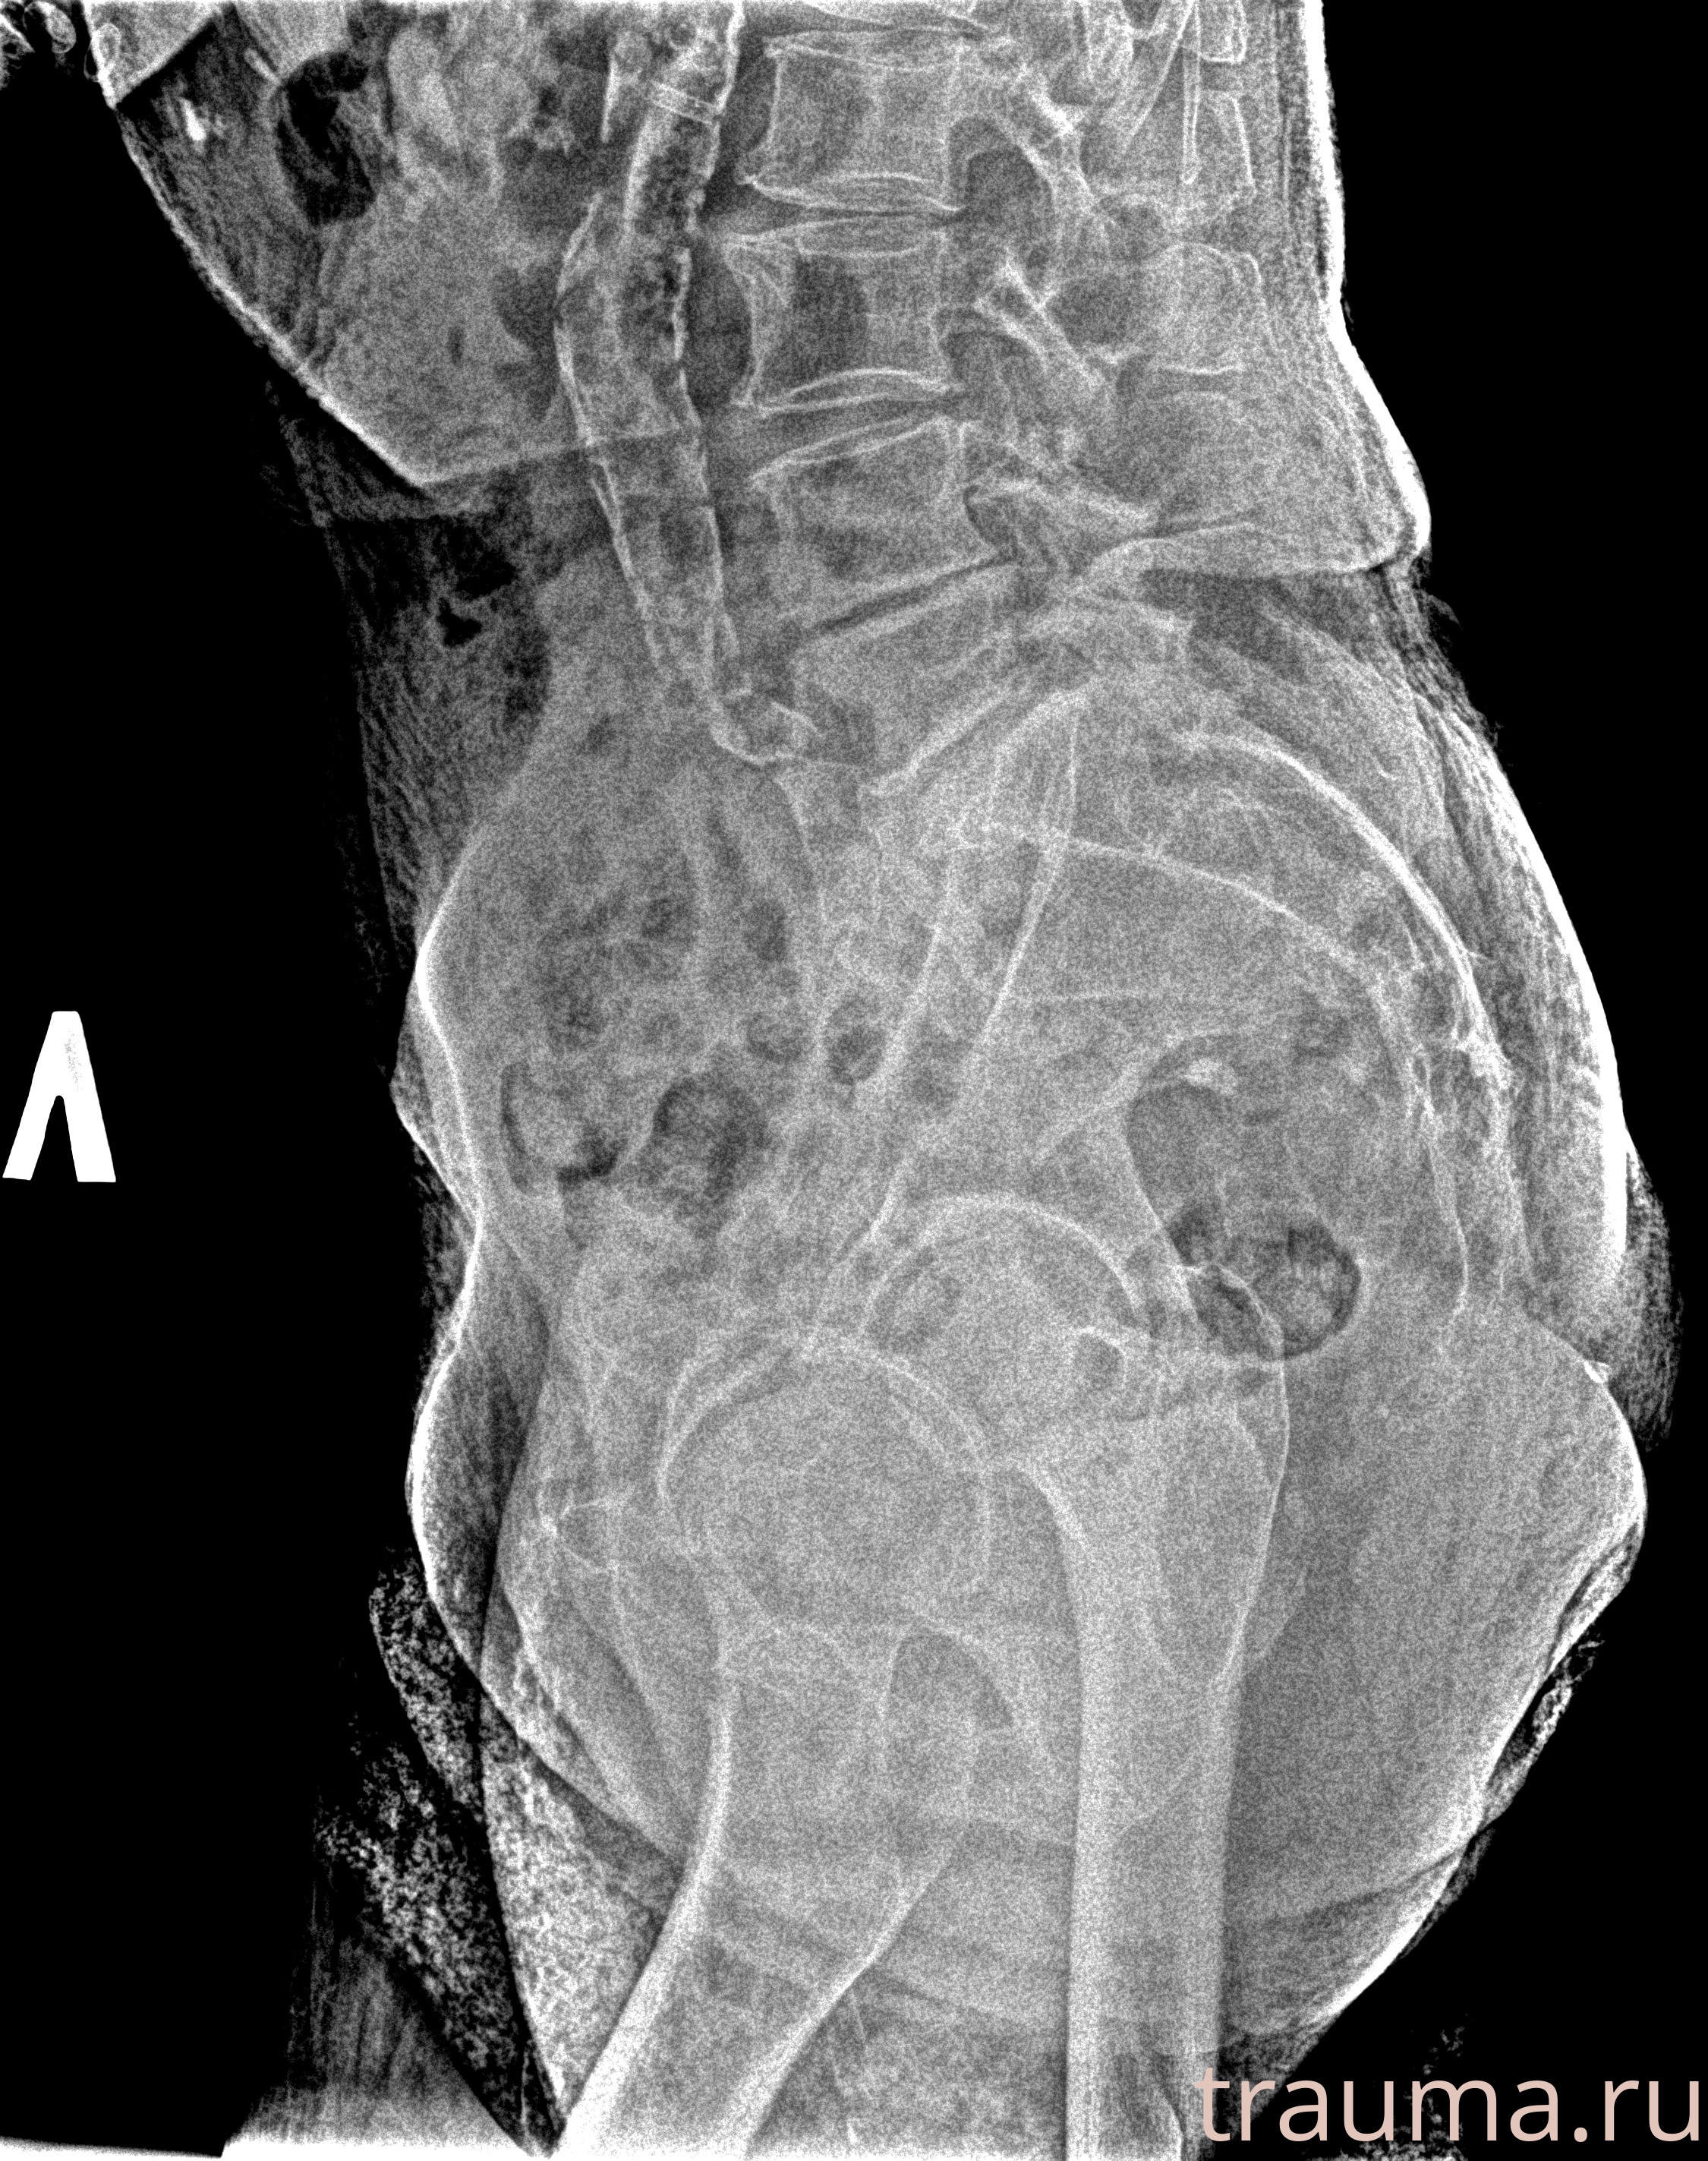

Рентген на дому: по вашему адресу приезжает врач-рентгенолог, травматолог-ортопед с мобильным рентгеновским аппаратом, проводит диагностику травмы или заболевания, делает необходимые рентгенограммы, дает рекомендации по дальнейшему лечению. Получить качественные снимки в домашних условиях возможно благодаря уникальной методике, разработанной МосРентген Центром для института  Склифосовского